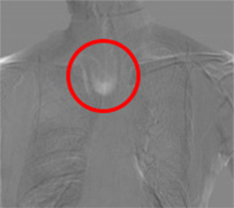

注意:赤枠は実際には表示されません。

肺門部裏は見落としやすく重要な読影ポイントですが、経時差分画像により一目で変化が確認出来ます。